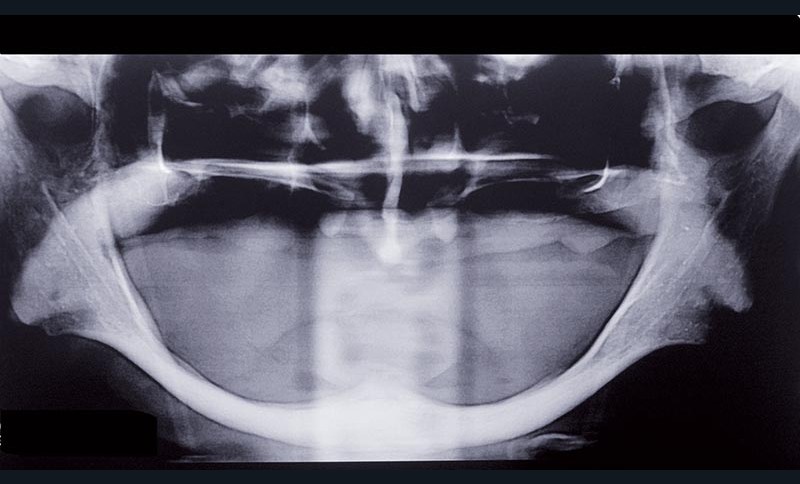

Il s’agit d’un phénomène parfaitement défini : perte de structure osseuse continue, cumulative, irréversible. C’est un phénomène impossible à contrecarrer, les étiologies proposées sont multiples, atteignant plus les femmes que les hommes mais dont les conséquences prothétiques sont majeures et difficiles à pallier (fig. 1).

Cliniquement la résorption se manifeste de deux manières.

La perte de volume osseux est accompagnée par les structures muqueuses des surfaces d’appui. Les reliefs osseux « stabilisateurs », tels que les crêtes, disparaissent, devenant dans certains cas négatifs, degré 6 de la classification Cawood et Howell…